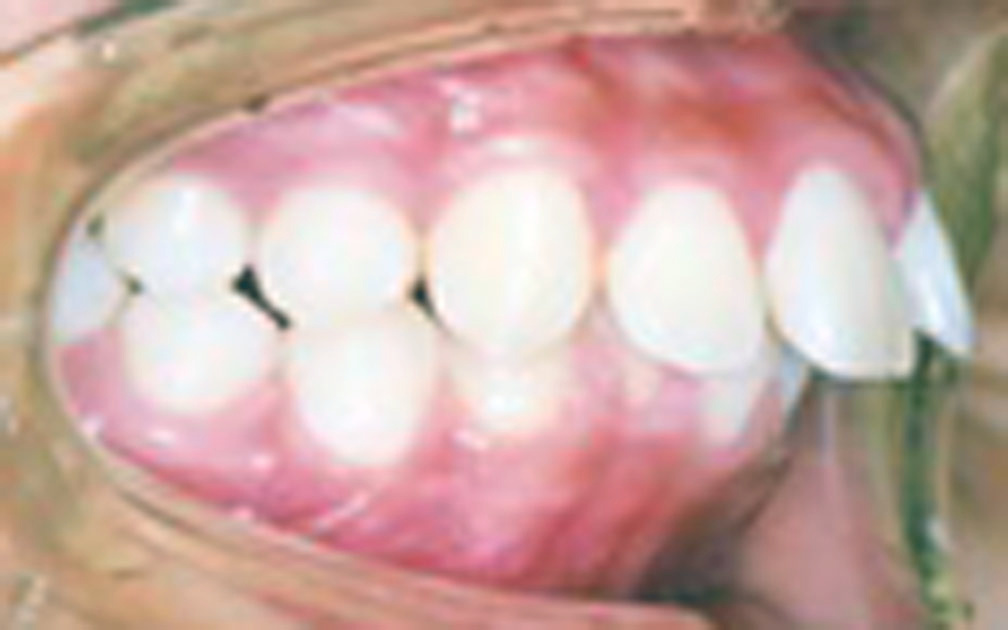

矯正の症例3 (診断名)叢生(ソウセイ)

(患者様の主訴)八重歯が気になる

(治療開始年齢)23歳4カ月

(主な治療装置)エッジワイズアプライアンス

(抜歯部位)上下第1小臼歯4本抜歯

(治療期間)1年10カ月

(治療費)¥805000

(個別リスク・副作用)叢生が著しいため動的治療後長期にわたる保定が必要となる。

歯牙の移動量が大きいため歯根が短根になるリスクがある。

叢生が改善されるまで、ブラッシングがしにくい状態が続くために齲蝕になるリスクがある